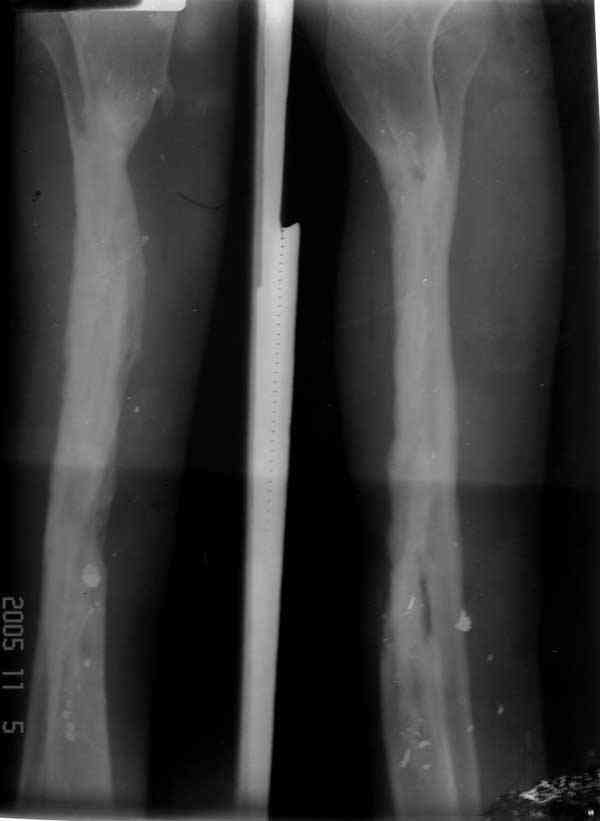

Отправлено Ласунский Сергей 30 Октябрь 2007, 23:53 РОСНИИТО им.Р.Р.Вредена

Пациентка с дефектом большеберцовой кости, возможно ли восстановление опороспособности нижней конечности? ДТП 1.5 года назад: открытый оскольчатый перелом средней трети левой голени с дефектом мягких тканей. Выполнены следующие операции в одной мз больниц города: 1.При поступлении ПХО и наложение АВФ 2.Нагноение резекция нежизнеспособной кости. 3.Пластика дефекта мягких тканей. 4.Попытка устранения дефекта по методу Илизарова, нагноение, радикальная хирургическая обработка, увеличение дефекта. 6 месяцев без признаков гнойного воспаления. В настоящее время иммбилизация гипсовой лонгетой до коленного сустава, функция коленного сустава сохранена, голеностопного нет.

Уважаемый Александр! Привет из Питера. Спасибо за быстрый ответ. Стержень с блокированием и кейдж, вариант изветный по литеоатуре, но очень короткий дистальный фрагмент и локальный остеопороз (будет ли хорошая фиксация?). Как считаешь вариант с фиксацией ложного сустава малоберцовой кости спластиной и ее предварительное утолщение свободным аутотрансплантатом 1\2 малоберцовой кости со здоровой стороны длиной 20-25 см., а после консолидации тибиализация малоберцовой кости?

Хотя для уменьшения размера дефекта (кейдж) можно было предложить предварительную однофокальное удлинение в проксимальном метафизе, потом применение стержня.

Стержень можно забить через голеностоп в таран, тогда удлинится и усилится короткий дистальный конец.

Если смелость больной достаточна для аппаратного лечения, тогда другой вариант, комбинация удлинения в проксимальном отделе большеберцовой и утолщения малоберцовой в нижней трети, где диаметр малоберцовой позволяет.